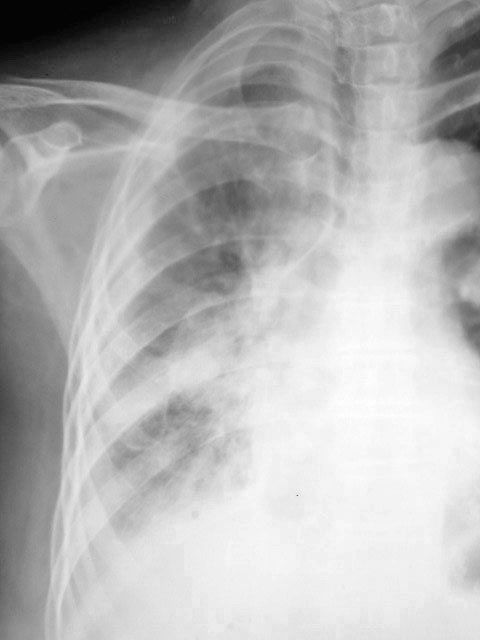

以下是引用马铃薯在2010-6-3 20:49:00的发言:[br]右侧肺门旁见1卵圆形团块样影,肺门结构不清,考虑右肺门旁肿块。右下肺感染。建议ct检查明确一下。[br]右侧胸膜炎。不排除胸膜转移。[br]心影增大。

以下是引用影像之剑在2010-6-3 22:56:00的发言:[br]右侧胸廓塌陷,胸膜增厚。右侧肺野透光度减低,右肺门影增大,似可见模糊块影。右膈面不清,右肋膈角消失。左肺透光度增高,肺内未见明显实质性病变。心影主动脉弓部突出,肺动脉段凹陷,左心缘向左下扩大。左膈清。[br][br]考虑右侧胸膜增厚,胸腔积液,右肺膨胀不全。右肺门模糊块影,建议ct。左肺代偿性气肿。主动脉型心。

以下是引用吴医师在2010-6-3 23:59:00的发言:[br]请与老片对比。如大致相同,考虑胸膜肥厚。如有明显不同,请ct检查。